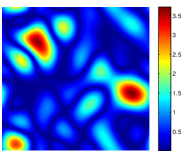

To illustrate this bound, suppose the minimal polynomial has degree , and we take Fourier samples from a square region. Then this requires at least Fourier samples to recover the edge set . Our numerical experiments on simulated data (see Fig. 1) indicate the above necessary condition might also be sufficient for unique recovery; that is, we hypothesize the minimal filter coefficients are the only non-trivial solution to the system of equations (13).

In Fig. 2 we demonstrate the ability of the proposed algorithm to recover a piecewise constant signal from few of its uniform low-resolution Fourier samples. We experiment on simulated data obtained from analytical MRI phantoms derived in [13]. We extrapolate from analytical Fourier samples of the Shepp-Logan phantom to a grid (20-fold undersampling), and recover the signal by performing a inverse DFT. Note that the ringing artifacts observed in the recovery are to be expected due to fact we are recovering exact Fourier coefficients of the signal, and could be removed with mild post-processing.